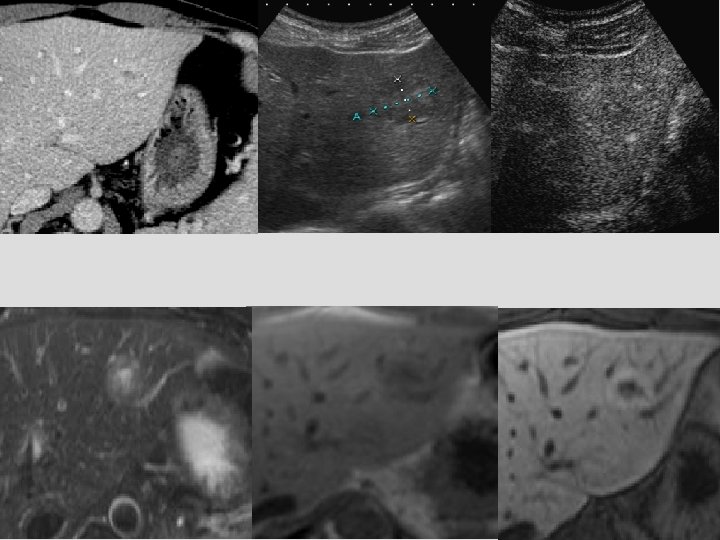

Hyperplasie nodulaire régénérative Anatomopathologie Formes mono-acinaire < 3 mm Hépatocytes hyperplasiques disposés autour d’un seul espace porte Formes multi-acinaire 3 mm à 4 cm Hépatocytes hyperplasiques disposés autour plusieurs espaces portes Vascularisation à prédominance artérielle Pathogénie Obstruction des branches portes intra-hépatiques

Obstruction des branches portes intrahépatiques 12 cures de Folfox : Dose cumulée Oxaliplatine 1050 mg/m² Syndrome d’obstruction sinusoïde (SOS)1 Obstruction sinusoïdale par des débris endothéliaux secondaire à la nécrose cellulaire Le plus souvent asymptomatique Hépatomégalie, ascite, augmentation de la bilirubine Aspect réticulaire du foie après injection, diminution de la captation des oxydes de fer (SPIO) Augmente le risque de résection hépatique : friable, congestif, « blue liver » 1 - Robinson, Eur Radiol 2009

Hyperplasie nodulaire régénérative et SOS Mécanisme physiopathologique proche entre SOS, HNR et péliose 2 HNR après traitement par oxaliplatine 3 Biopsie Absence de localisation tumorale Absence de fibrose périnodulaire Hépatocytes hyperplasiques 2 - De Leve et al, Liver Dis 2002 3 - Hubert et al, Liver Int 2007

HNR multifocales